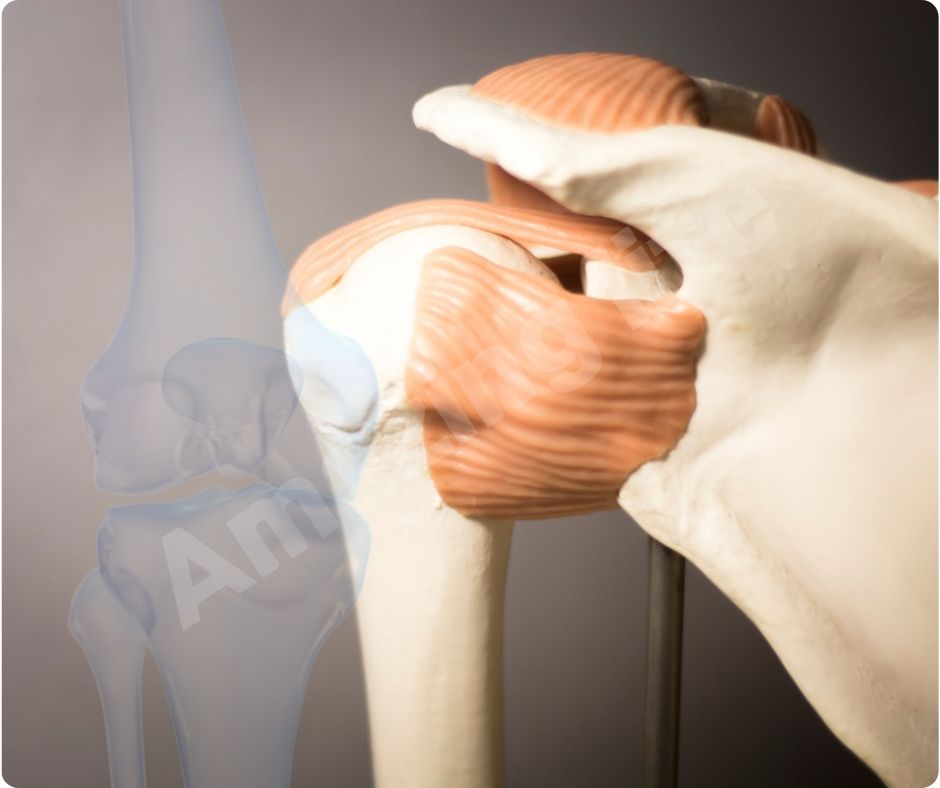

글루코사민은 신체 내에서 자연적으로 생성되며, 연골의 주요 구성 요소로 관절의 유연성과 기능을 유지하는 데 중요한 역할을 합니다. 특히 관절염과 같은 관절 문제를 예방하거나 완화하는 데 유용한 보충제로 많이 사용됩니다.

연골 보호 및 재생

글루코사민은 연골 조직의 구성 요소로서 연골의 손상을 막고 재생을 촉진합니다. 이는 특히 고령자나 관절에 많은 부담이 가는 운동을 하는 사람들에게 중요합니다. 글루코사민의 연골 보호 효과는 관절염의 진행을 늦추고 삶의 질을 향상시키는 데 큰 도움을 줍니다.